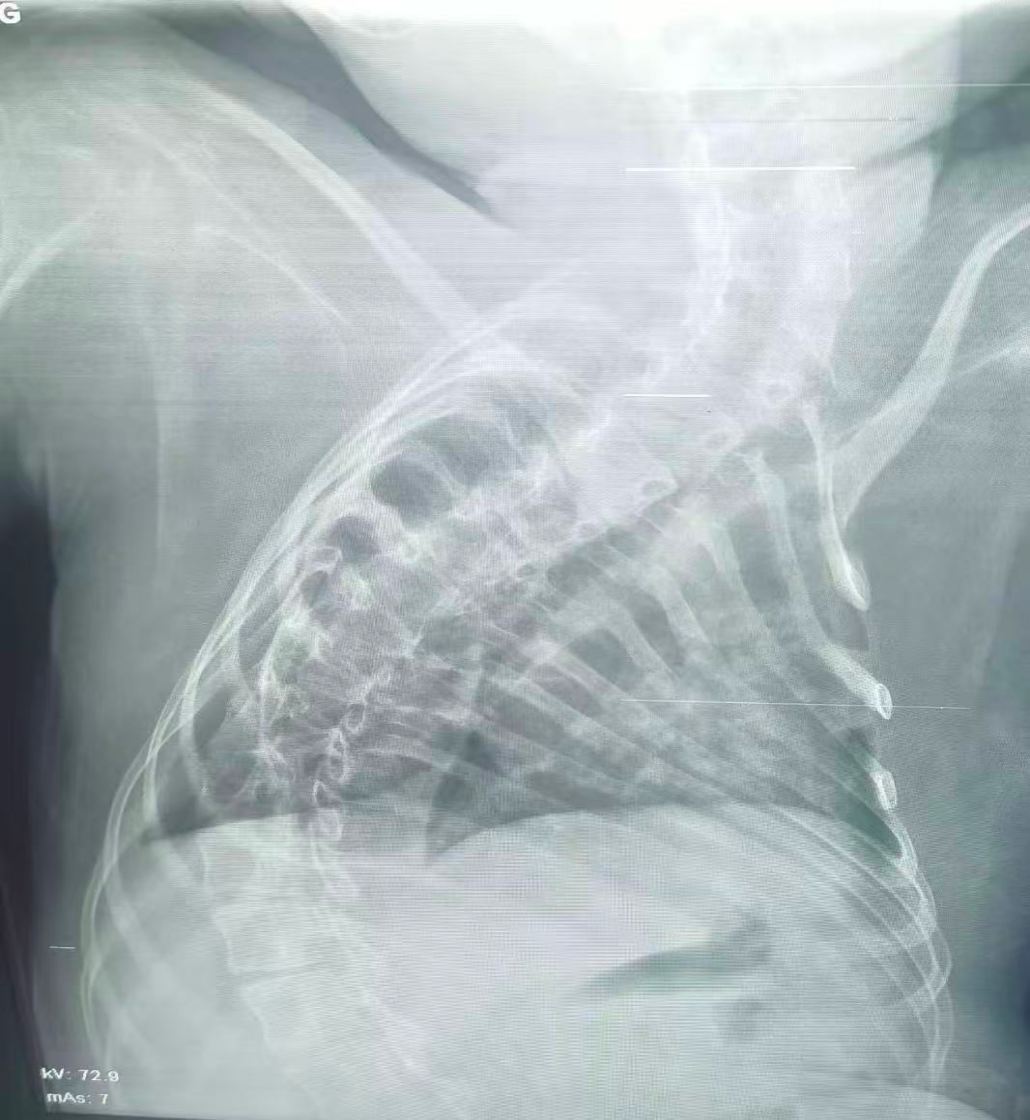

治療前

該患兒因患脊髓性肌萎縮癥長期臥床,呼吸肌已嚴(yán)重?zé)o力,自主呼吸微弱且?guī)缀鯁适Э人耘盘的芰?,此次并發(fā)支氣管肺炎后,肺部感染迅速加重,生命已然懸于一線。更棘手的是,嚴(yán)重的脊柱側(cè)彎使患兒胸廓畸形、氣道解剖結(jié)構(gòu)明顯移位,常規(guī)纖支鏡進(jìn)鏡路徑完全失效,扭曲狹窄的氣道如同縱橫交錯(cuò)的“迷宮”,每一步操作都必須精準(zhǔn)到毫米級(jí)別。